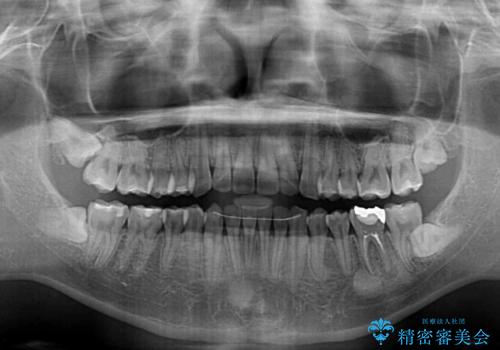

- 前歯のクロスバイトを気にして来院された患者様です。

骨格的には問題がなかったため、インビザラインを用いて咬み合わせを改善していくこととしました。

インビザライン特有の、奥歯の咬み合わせの問題もなく、しっかりと歯列を改善することができました。

舌側転位している上顎側切歯(内側に引っ込んでいる真ん中から2番目の歯)は、インビザラインが最も移動を苦手とする歯であり、これ以上の改善を望まれる場合にはワイヤー矯正、あるいはワイヤー矯正の併用をお勧めいたします。